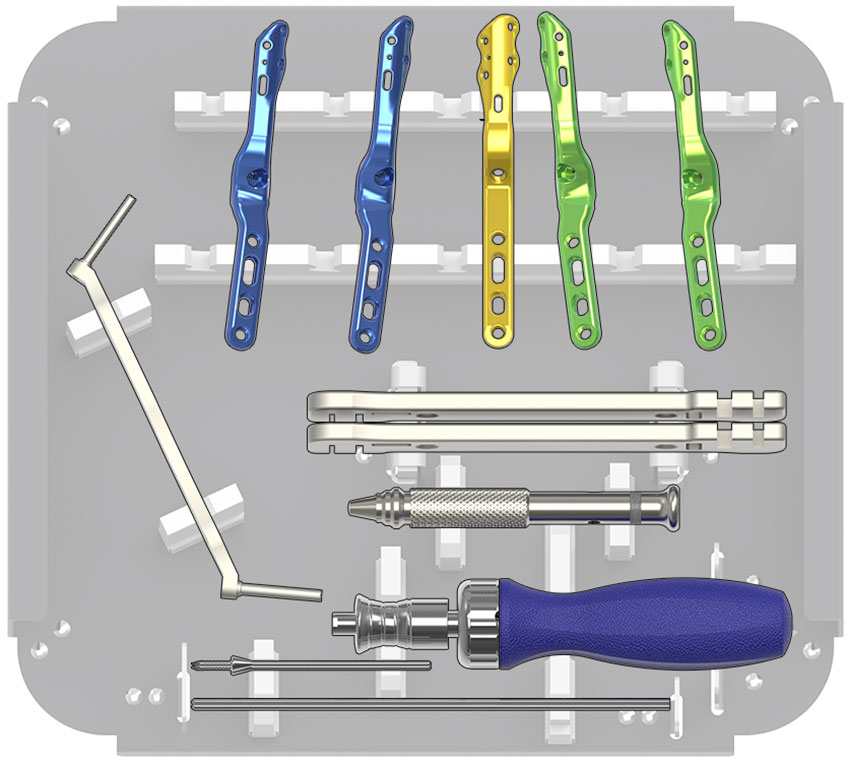

Total Wrist Fusion Plate – Wrist Fracture Fixation – TriMed Inc.

Total Wrist Fusion Plate – Wrist Fracture Fixation – TriMed Inc.

Total Wrist Fusion Plating System | Acumed

TriMed Total Wrist Fusion Plate – CliniLab

TriMed Total Wrist Fusion Plate – CliniLab

TriMed Total Wrist Fusion Plate – CliniLab

HW-Total-Wrist-Fusion-Plating-System-tray-1 | Acumed

Trimed Total Wrist Fusion System | LMT Surgical Australia & New Zealand

Total Wrist Fusion Plating System – SUMMED Finland Oy

Total Wrist Fusion Plating System – SUMMED Finland Oy